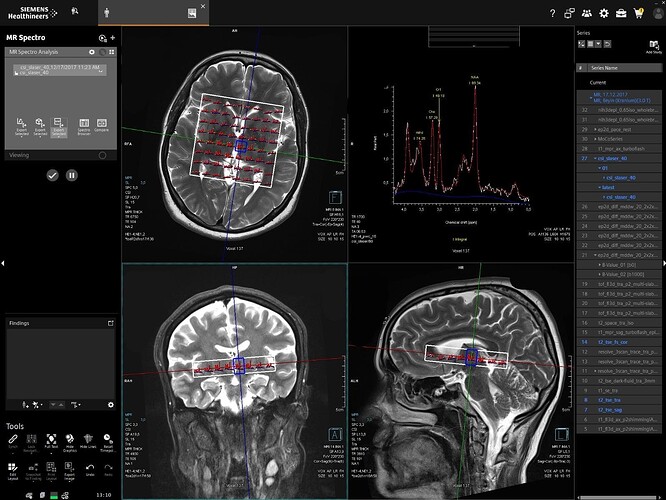

Last week, I tried several approaches to derive orientation values, and I think I have found a method to overcome this issue. Instead of using the SlabOrientation values, I derived rotation angles (in radians) from the RowVector and ColumnVector matrices by decomposing them into Euler angles. I tested this approach on multiple datasets, and so far it appears to work well.

For voxel positioning, I used the MidSlabPosition matrix instead of PositionVector. Apart from these changes, I did not make any major modifications to the existing code.